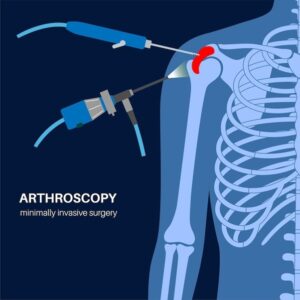

What Are Minimally Invasive Orthopedic Surgeries? Minimally invasive orthopedic surgery is a modern way to treat bone and joint problems. In these surgeries, doctors use

Shoulder arthroscopy is a specialized medical procedure used to diagnose and treat problems related to shoulder joint. It is a MIS (minimally invasive surgery) that